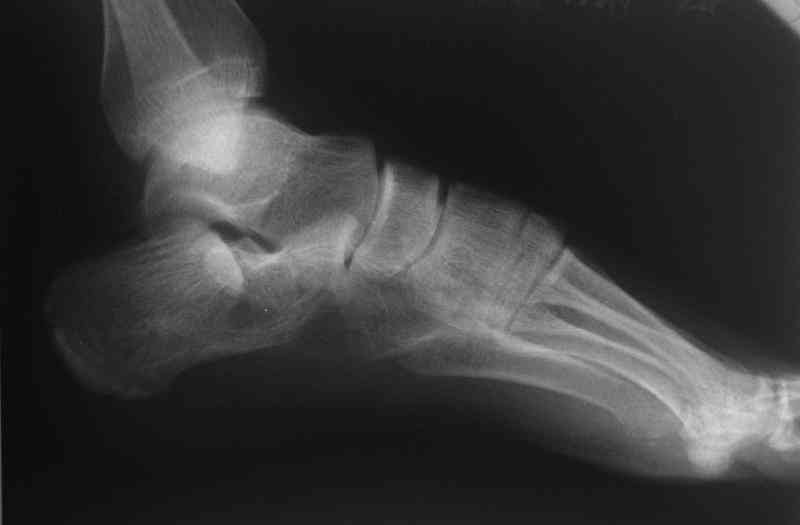

Its a comminuted one.

I would have a CT prior 2 surgery(If u have to postpone a surgery for it - I would operate without one)

I myself would reduce it with EX-FIX and depending on the result would consider a plate on the table.

MOST OF MY COLLEGUES WOULD OPEN IT LATERALLY( a flap) and having a proper reduction would put a plate.

Если нет опыта в остеосинтезе пяточной пластиной то лучше начать с экскохлеации полости кистозного образования и заполнения его остеоиндукторами Коллапан, Тутопласт, etc.Закрытая репозиция с рентгенконтролем на столе и перкутанная фиксация спицами пяточного бугра с фиксацией в эквинусе могут дать вполне приемлемый результат.

Сустав похоже интактен, киста под вопросом,даже при наличии опыта остесинтеза пластиной, в данном случае выведение правильного угла и фиксация спицами более чем достаточно, да и намного спокойнее сон у хируга.

Перелом безусловно внутрисуставной. Киста-не киста принципиального значения не имеет.